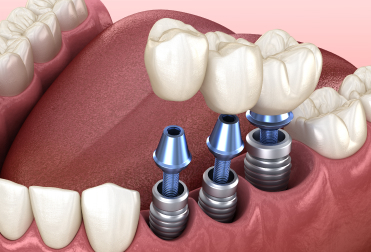

- Implants are strong. Titanium strong. Once the titanium implant post is placed, it acts as the “root” for your new tooth, bonding to your jawbone and creating a stable foundation for your new restoration.

- They are multipurpose. In addition to restoring a single tooth, two to four implants can act as anchors for larger dental restorations, such as full-arch implant-supported dentures or a partial bridge.